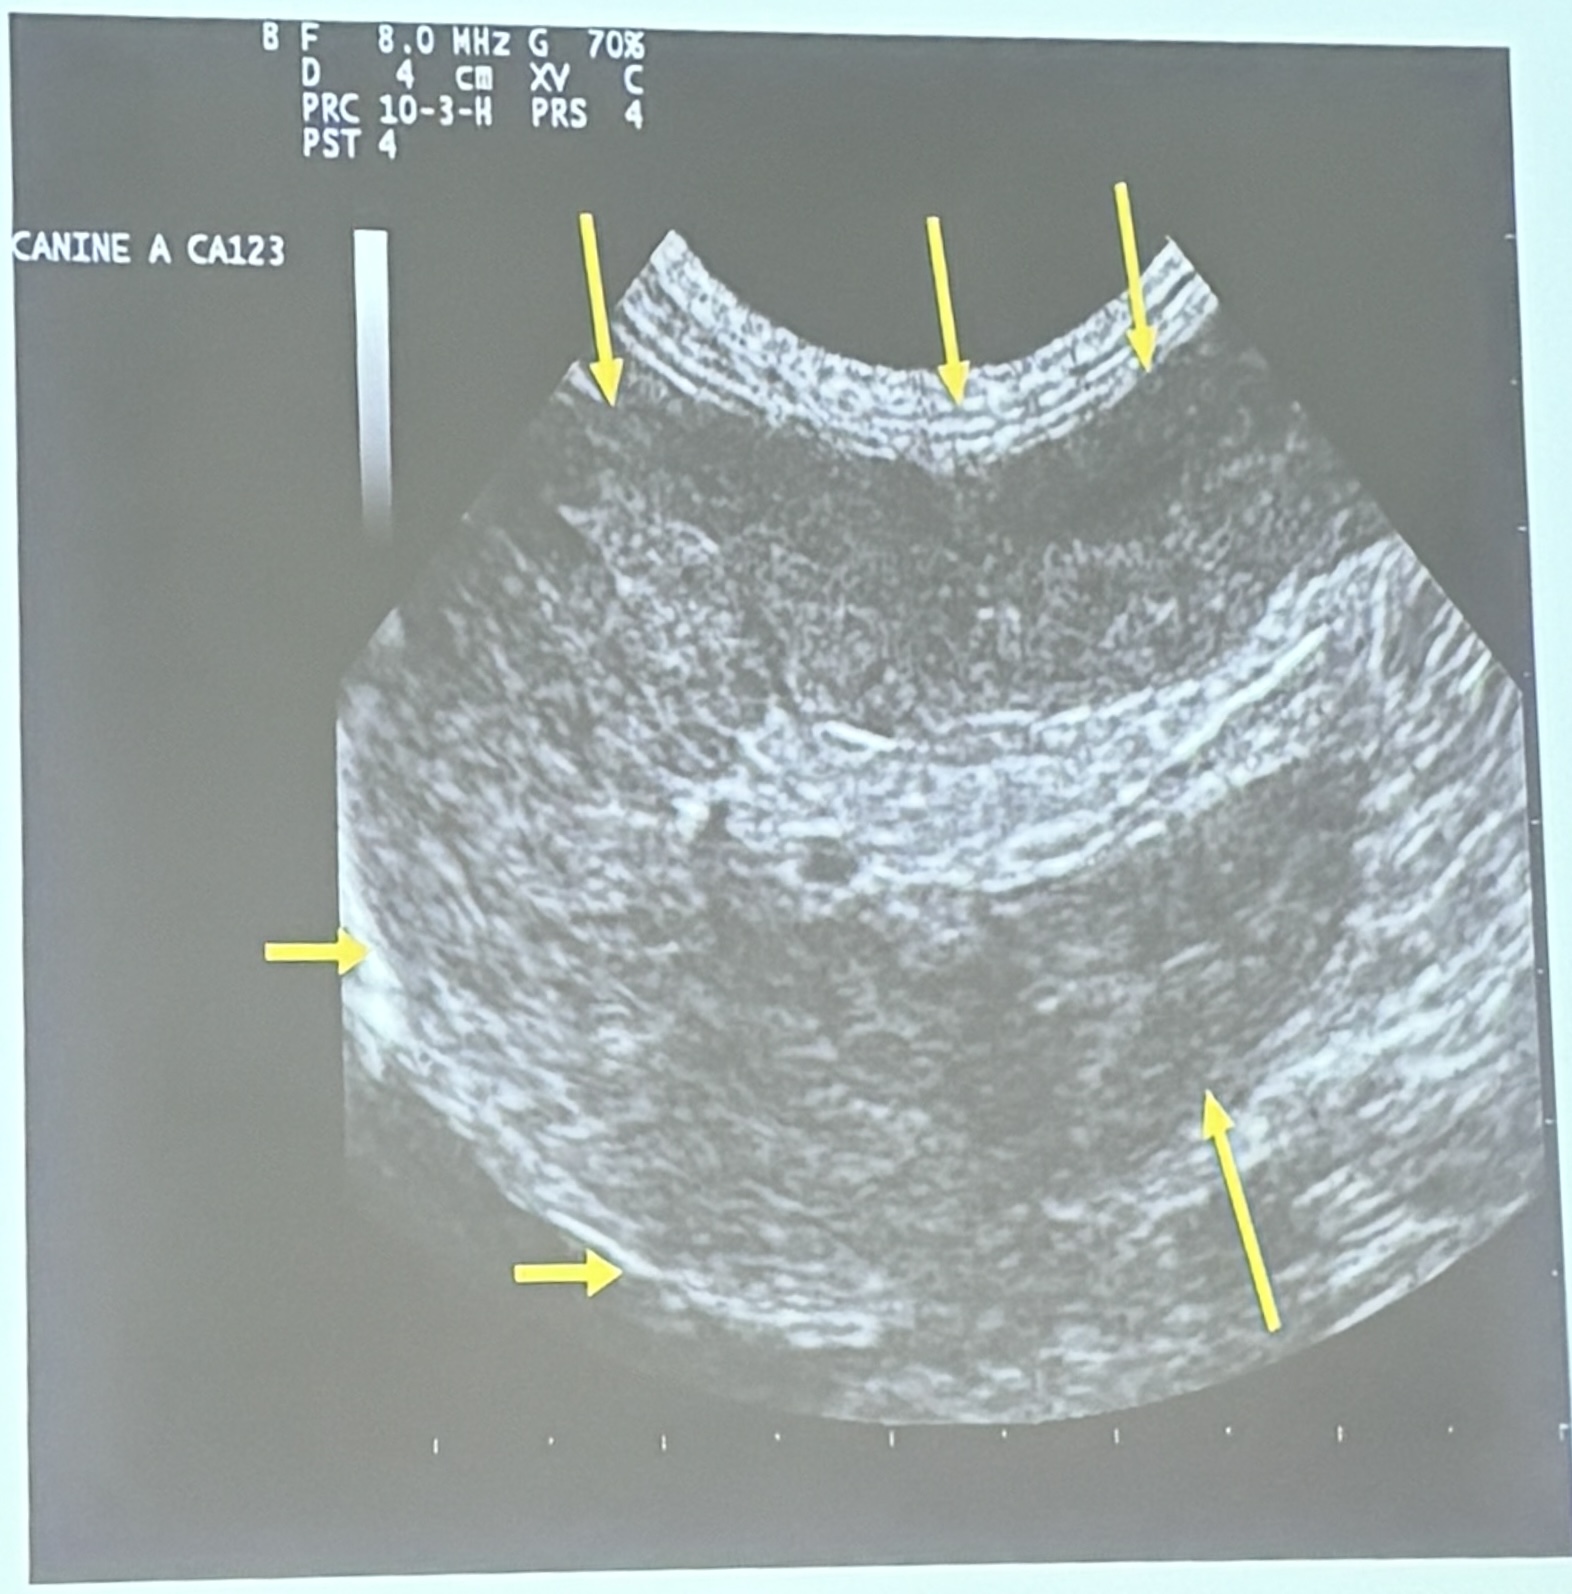

This is a longitudinal scan of the spleen of a 13yo FS Siamese cat presenting with a history of abdominal distension & anorexia. What are the ultrasonographic findings?

Splenomegaly / heterogenous echogenicity